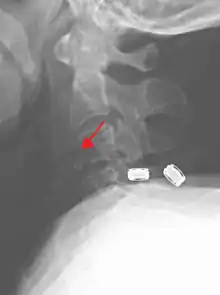

Teardrop fracture of C3 (lateral X ray)